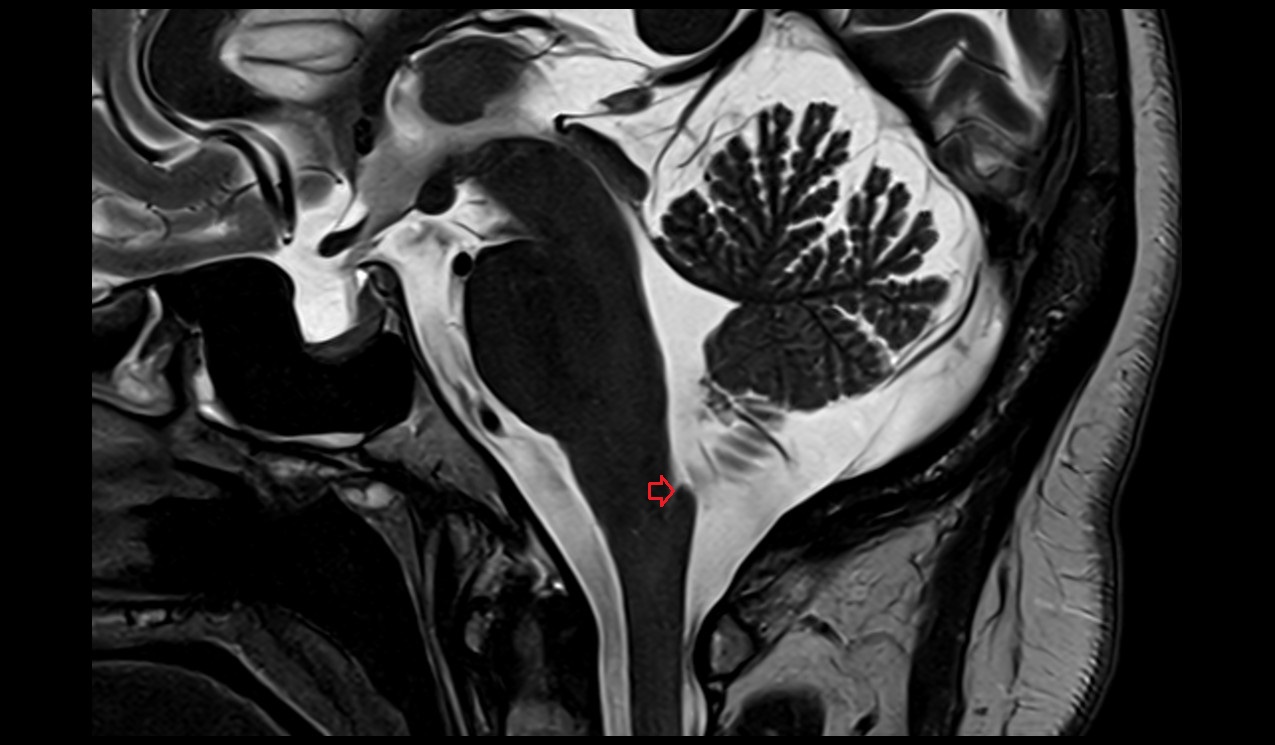

- Conus medullaris

- Spinal cord